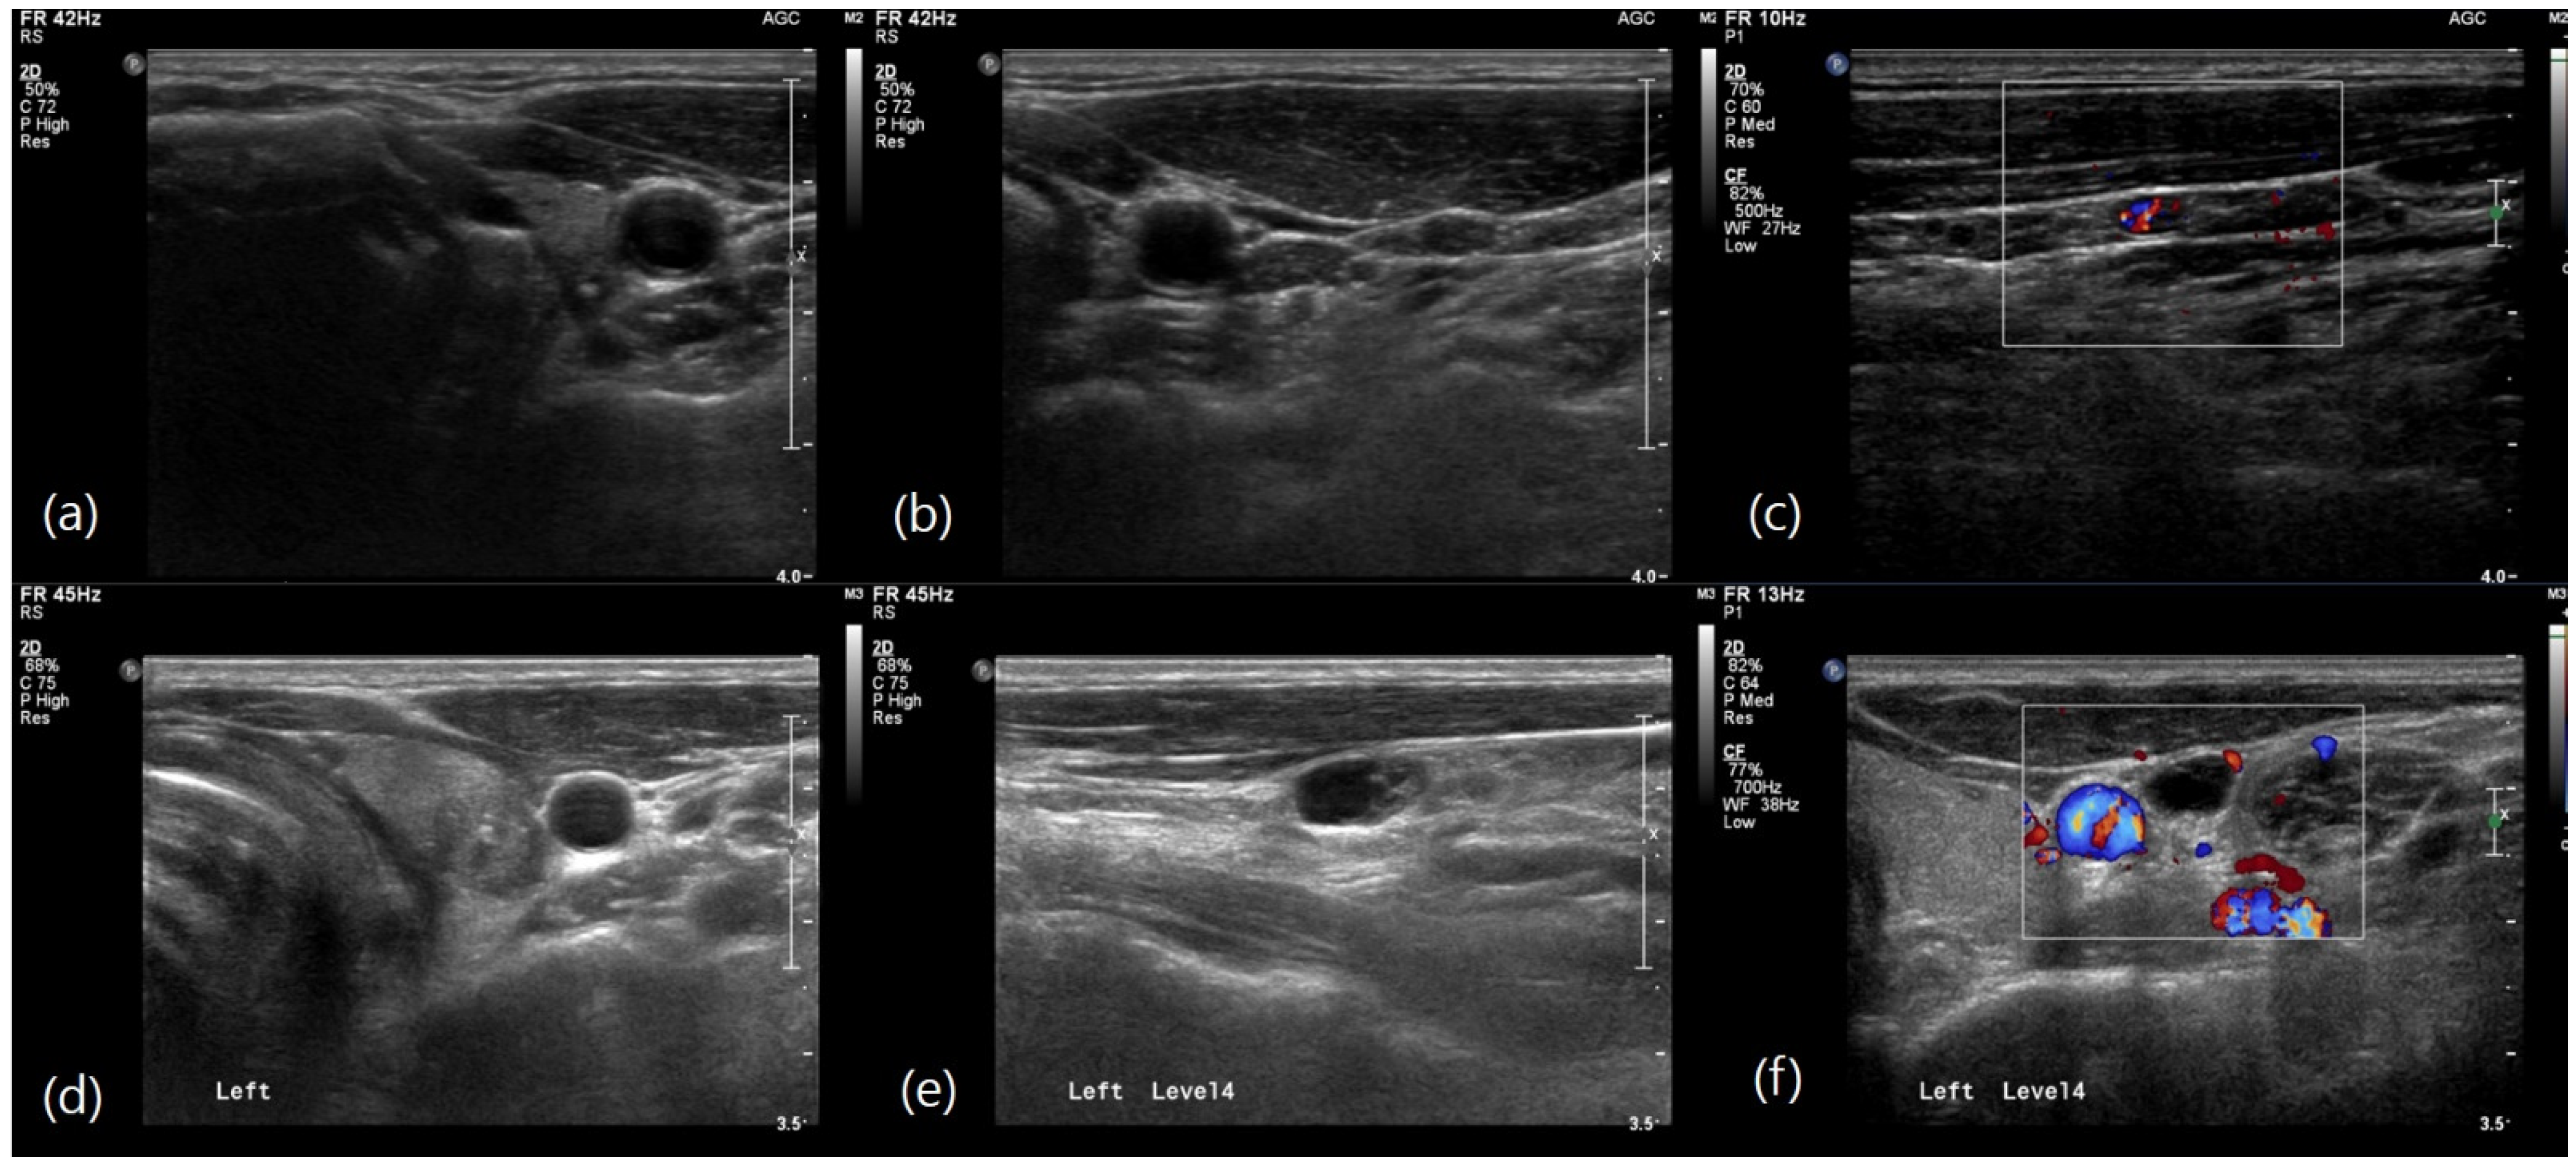

Figure 3. Haematoxylin-Eosin (HE) staining images of the thyroid and metastatic lymph nodes in a 55-year-old man with papillary thyroid carcinoma shown in Figure 2a–c. (a) Papillary carcinoma in thyroid (HE staining). (b) Cytoplasmic expression of thyroglobulin in papillary thyroid carcinoma by immunohistochemistry. (c) Nuclear expression of TTF-1 in papillary thyroid carcinoma by immunohistochemistry. (d) Metastatic papillary thyroid carcinoma in a cervical lymph node (HE staining). (e) Cytoplasmic expression of thyroglobulin in metastatic carcinoma by immunohistochemistry. (f) Focal positivity of TTF-1 in metastatic carcinoma by immunohistochemistry. Scale bar in figures represent 200 μm.

Multivariable logistic regression analysis identified several independent predictors of level II LN metastasis. In the preoperative model (Table 3), larger tumor size (OR, 1.031; 95% CI: 1.011–1.051; p = 0.002) and nonparallel tumor shape (OR, 1.963; 95% CI: 1.322–2.915; p = 0.001) were significantly associated with level II metastasis. Additionally, the involvement of multiple LN levels and level III were strong predictors with odds ratios of 1.906 (95% CI: 1.242–2.925; p = 0.003) and 1.867 (95% CI: 1.223–2.850; p = 0.004) respectively. In the postoperative model (Table 4), non-conventional pathology was a significant predictor (OR, 1.951; 95% CI: 1.121–3.396; p = 0.018). The presence of extrathyroidal extension (OR, 1.867; 95% CI: 1.060–3.331; p = 0.031) and a higher LN ratio (OR, 1.057; 95% CI: 1.039–1.076; p < 0.001) were also significantly associated with level II metastasis. These findings highlight the importance of comprehensive preoperative evaluation, including a detailed assessment of tumor size, shape, pathology, and LN characteristics, to identify patients at higher risk of level II LN metastasis (Figure 2 and Figure 3).